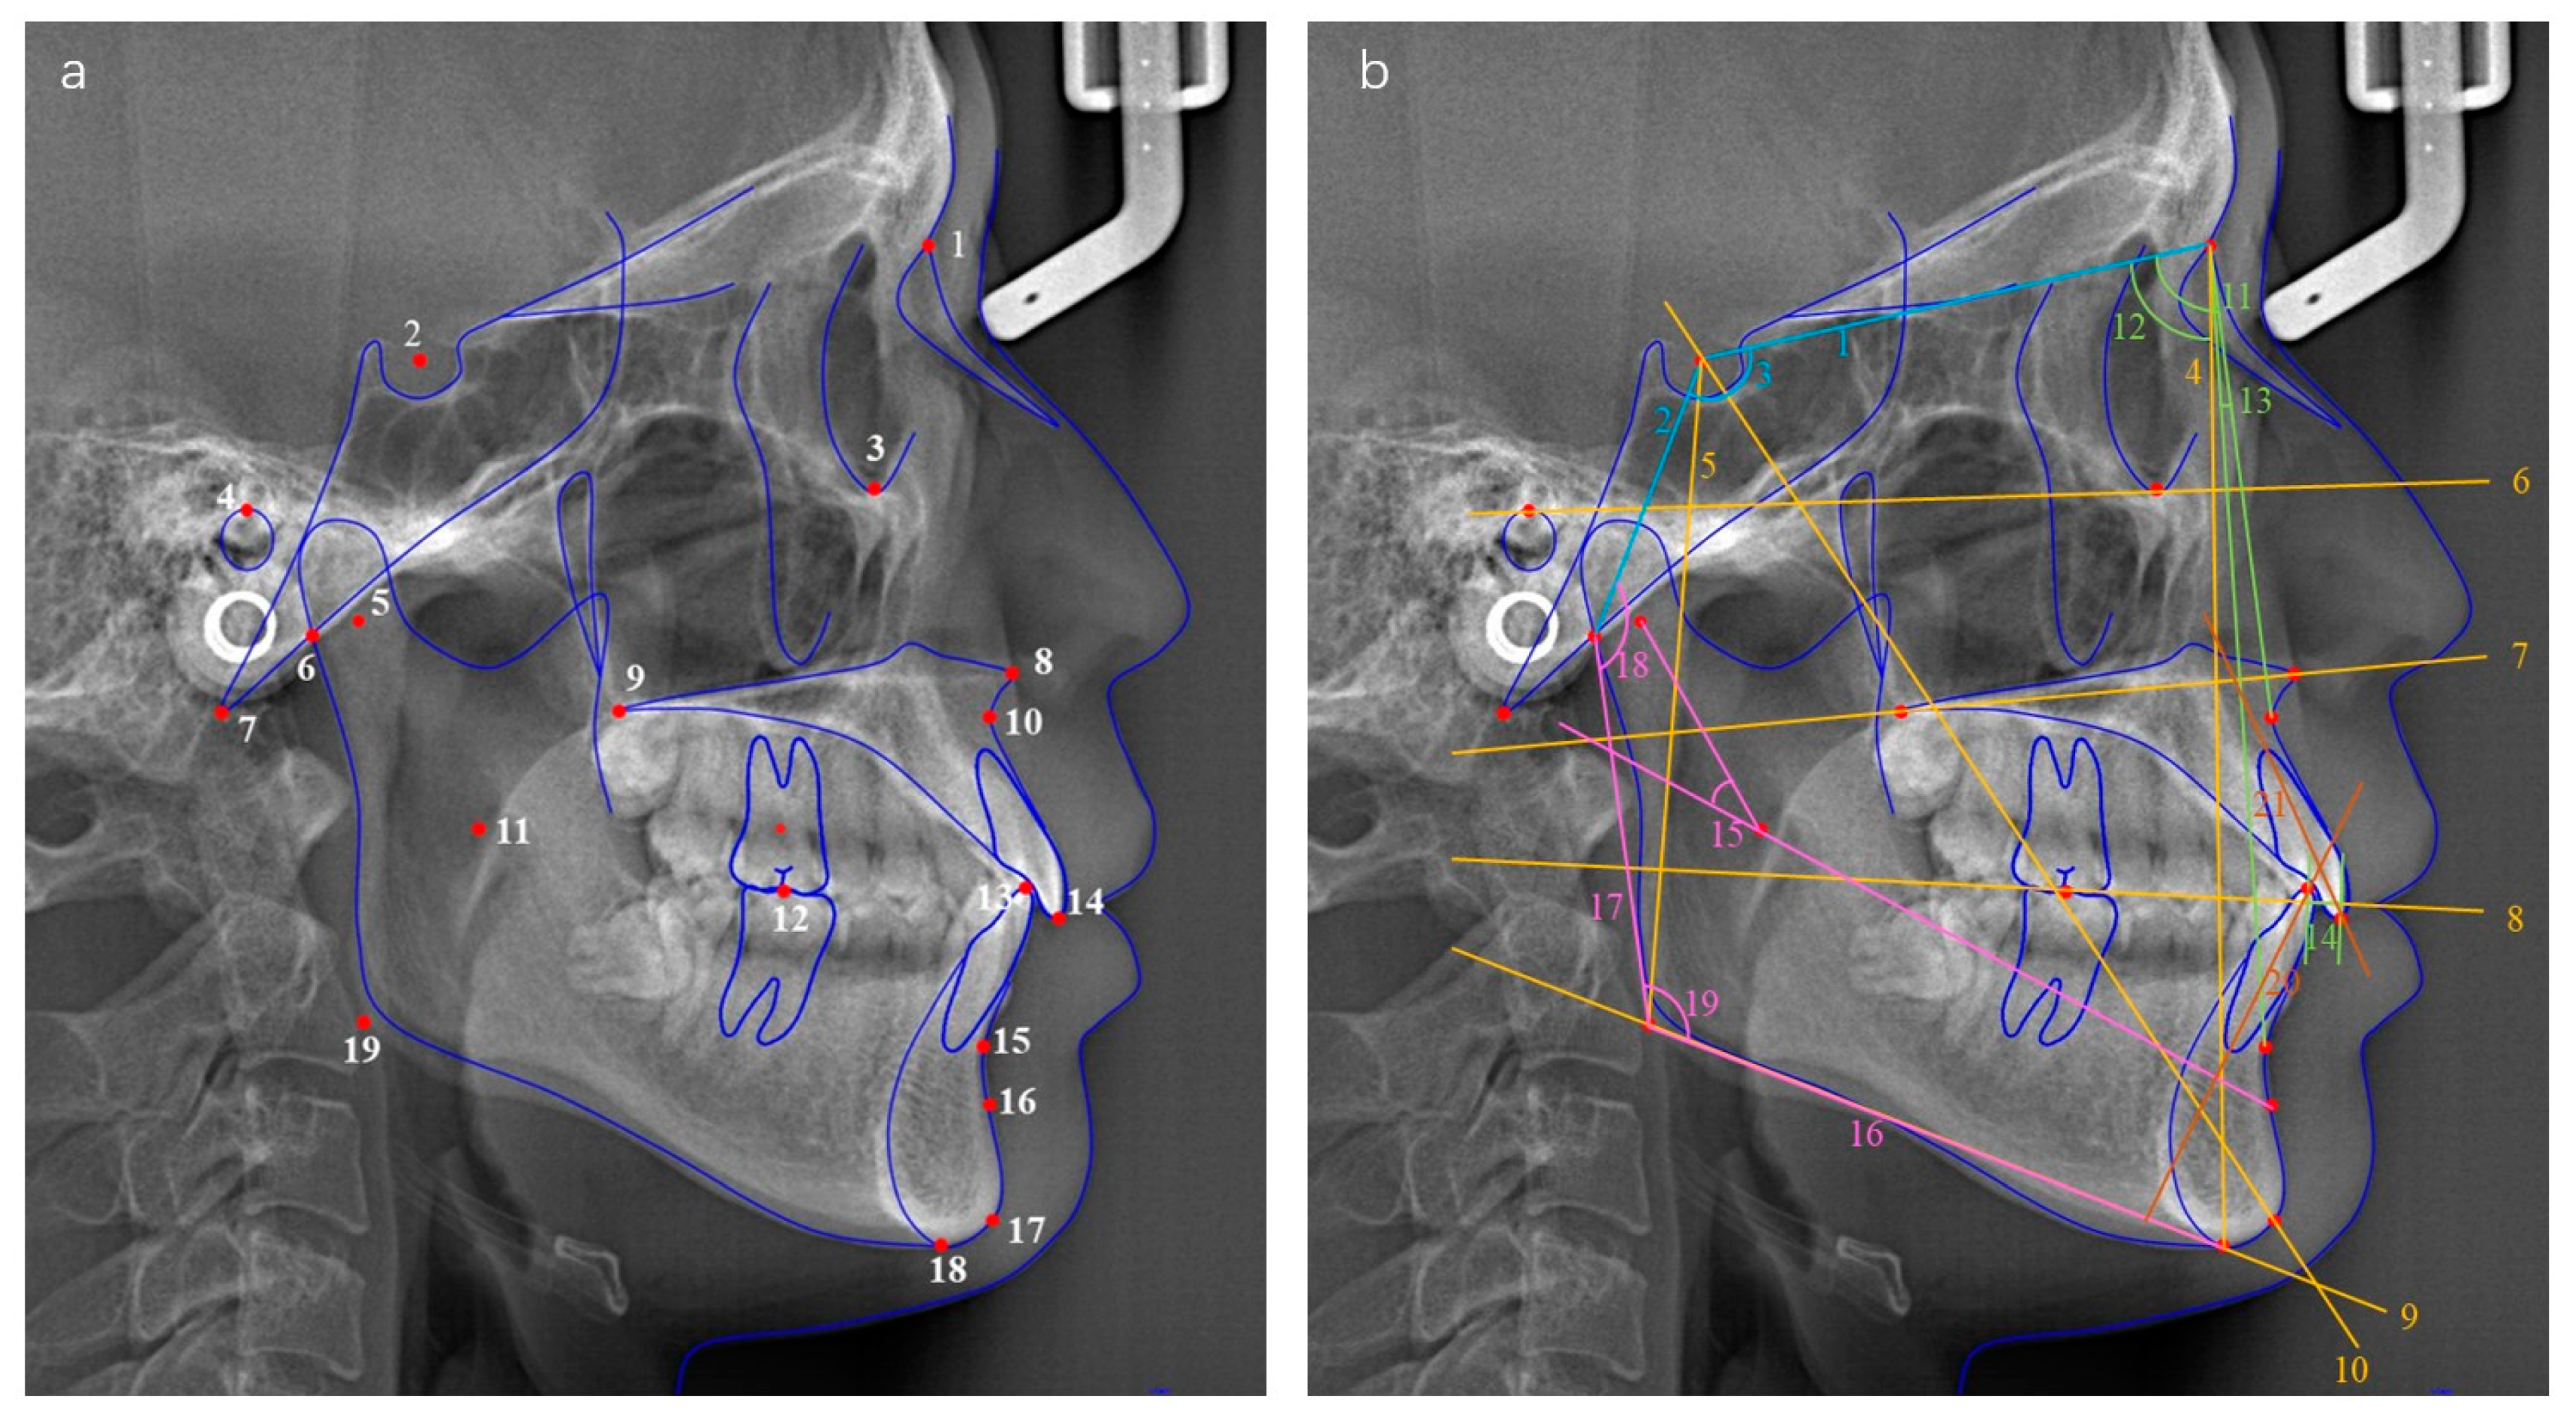

2.3. Cephalometric Evaluation

| Measurements | Definitions |

|---|---|

| 1. Cranial base | |

| Anterior cranial base length (mm) | S–N, distance between sella (S) and nasion (N) |

| Posterior cranial base length (mm) | S–Ar, distance between sella (S) and articulare (Ar) |

| Saddle angle (°) | Angle formed by S–Ar line and S–N plane |

| 2. Vertical relationship | |

| Anterior facial height (mm) | N–Me, distance between nasion (N) and menton (Me) |

| Posterior facial height (mm) | S–Go, distance between sella (S) and Gonion (Go) |

| Facial height index (%) | Posterior facial height/anterior facial height × 100% |

| Y-axis angle (°) | Angle formed by S–Gn line and FH plane |

| Palatal plane angle (°) | PP–FH, angle formed by PP plane and FH plane |

| Mandibular plane angle (FMA) (°) | MP–FH, angle formed by MP plane and FH plane |

| Occlusal plane angle (°) | OP–FH, angle formed by OP plane and FH plane |

| 3. Sagittal relationship | |

| Sella–nasion–point A angle (SNA) (°) | Angle formed by nasion–A line and SN plane |

| Sella–nasion–point B angle (SNB) (°) | Angle formed by nasion–B line and SN plane |

| Point A–nasion–point B angle (ANB) (°) | Angle formed by nasion–A line and nasion-B line |

| Wits (mm) | Distance between vertical lines from A point and B point to OP plane |

| 4. Mandible position and morphology | |

| Mandibular Arc (°) | Dc–Xi–Pm, angle formed by Dc–Xi line and Xi–Pm line |

| Mandibular body length (mm) | Go–Me, distance between gonion (Go) and menton (Me) |

| Ramus height (mm) | Ar–Go, distance between articulare (Ar) and gonion (Go) |

| Articular angle (°) | S–Ar–Go, angle formed by S–Ar line and Ar–Go line |

| Gonial angle (°) | Ar–Go–Me, angle formed by Ar–Go line and MP plane |

| 5. Dental relationship | |

| Interincisal Angle (°) | U1–L1, angle formed by the long axes of the upper and lower incisor |

| Incisor mandibular plane angle (IMPA) (°) | L1–MP, angle formed by the long axes of the lower incisors and MP plane |

| Frankfort mandibular incisor angle (FMIA) (°) | L1–FH, angle formed by the long axes of the lower incisors and FH plane |

| Overbite (mm) | Horizontal distance between the upper and lower incisal edges |

| Overjet (mm) | Vertical distance between the upper and lower incisal edges |